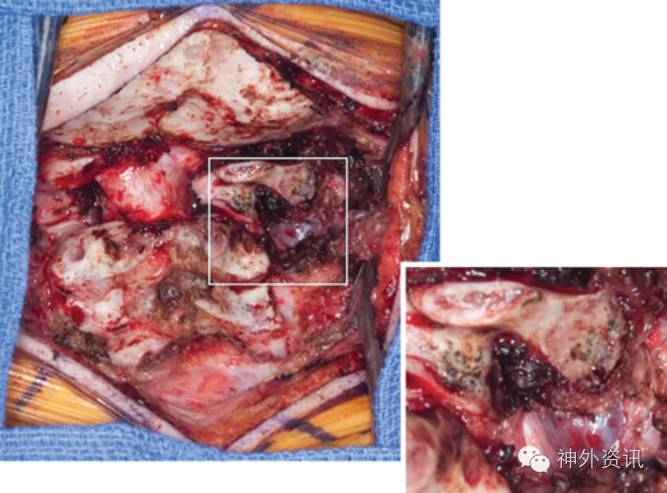

1例脊柱骨肉瘤的手术治疗